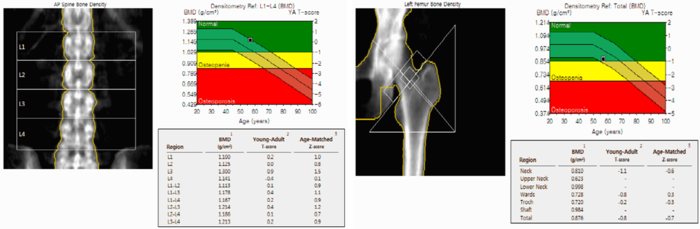

골밀도 검사 결과는 일반적으로 T-score라는 지표를 통해 판단합니다. T-score는 건강한 젊은 성인의 평균 골밀도와 비교하여 현재 골밀도 상태를 평가하는 지표입니다.

T-score 기준은 다음과 같습니다.

- -1.0 이상 : 정상

- -1.0 ~ -2.5 : 골감소증

- -2.5 이하 : 골다공증